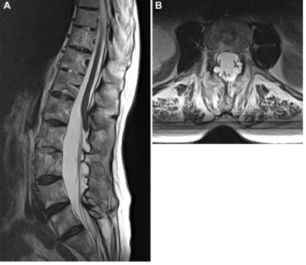

Ⅰ型:硬膜囊憩室表现为硬膜囊外侧或后方的囊状膨出(图2);通过缺损的硬膜与蛛网膜下腔相通,硬膜囊憩室的壁可能含有蛛网膜和硬膜成分,大多数发生在胸椎。憩室内通常没有神经根,但神经根可能是憩室壁的一部分。治疗的关键是缝合或夹闭硬膜的缺损。

![]()

图2. 73岁女性,背部疼痛2年半伴右下肢无力。A.MRI-T2加权矢状位显示T12-L2巨大硬膜囊憩室;B.MRI-T2加权轴位显示,硬膜囊被挤向前方,憩室内分隔;C.切除T12-L1椎板后的术中照片示,憩室的上端(白箭)和中部扩张进入椎间孔区(箭头);D.打开憩室并向尾端分离后可见硬膜缺损(白箭)和右侧L1神经根的内缘(箭头);E.硬膜缺损予以缝合(白箭);F.术后复查MRI-T2加权显示硬膜囊减压彻底。